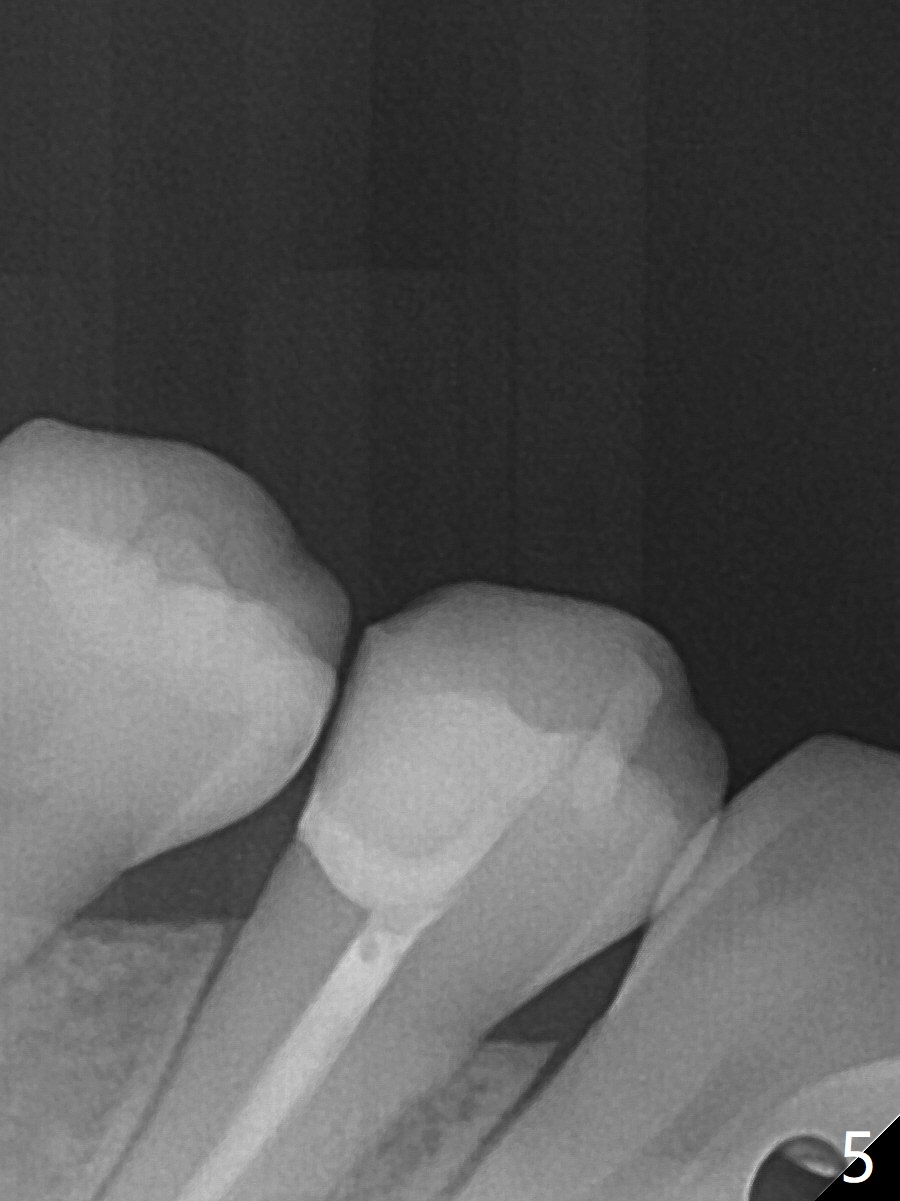

25岁硕士生,女,要求右下4补牙(图一:第一前磨牙),经过解释,欣然接受根管治疗。后者要领基本四条:无菌,根管笔直通畅,使用根尖定位仪和旋转式锥形扩大针和锥形牙胶尖。为了无菌,局麻后常规使用橡皮障(图二 *)。防止断针,尤其是旋转式锥形扩大针,根管治疗开口尽量大(图二箭头),保持扩大针笔直。开始根尖定位仪有点毛病,使用15号锉测定根管长度,不小心超越根尖大约3毫米(图三)。后来倒退4毫米,并得到根尖定位仪证实,主牙胶尖(30/.06)好像长度合适(图四),反复冲洗,最后再插入一个细牙胶尖一次性完成根管治疗和补牙(图五,六)。